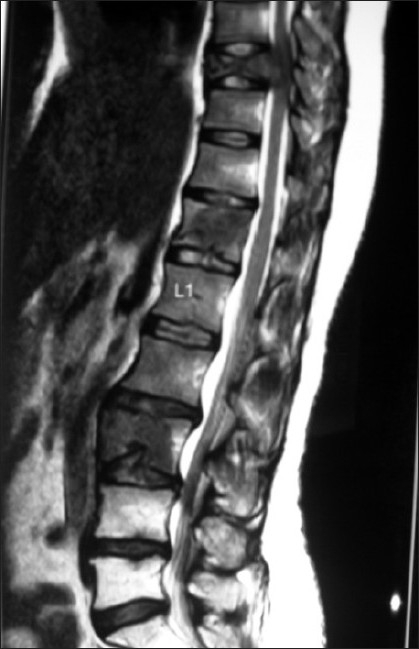

A 41-year-old premenopausal lady diagnosed as FIGO Stage Ic grade III endometroid adenocarcinoma [Figure 1] of uterus was referred for adjuvant radiotherapy after wertheims hysterectomy. Hormone receptor study was negative. She received adjuvant whole pelvis RT and vaginal brachytherapy as per NCCN practice guidelines V.1.2008. One month after treatment, she presented with weakness of lower limbs, fatigue, giddiness and visual complaints of one week duration. MRI of the spine revealed metastases to thoracolumbar vertebrae with cord compression. [Figure 2] and multiple liver metastases [Figure 3]. MRI of brain showed multiple brain metastases [Figure 4]. Subcutaneous lesions were found on scalp and infra axillary region. Fine needle aspiration cytology confirmed them to be metastatic [Figure 5]. She was treated with palliative radiotherapy to spine and brain.

| Figure 2 MRI of spine showing the collapse of dorsal 9 vertebra with cord compression